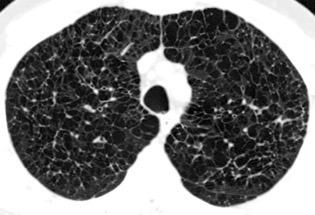

< Volumen pulmonar

Síndrome antisintetasa

(Miositis anti Jo-1).

Artralgias migratorias, Miositis, “Manos de mecánico”, Raynaud y Enfermedad

intersticial pulmonar (>70%).

Waseda Y et al.. Eur J Radiol. 2016